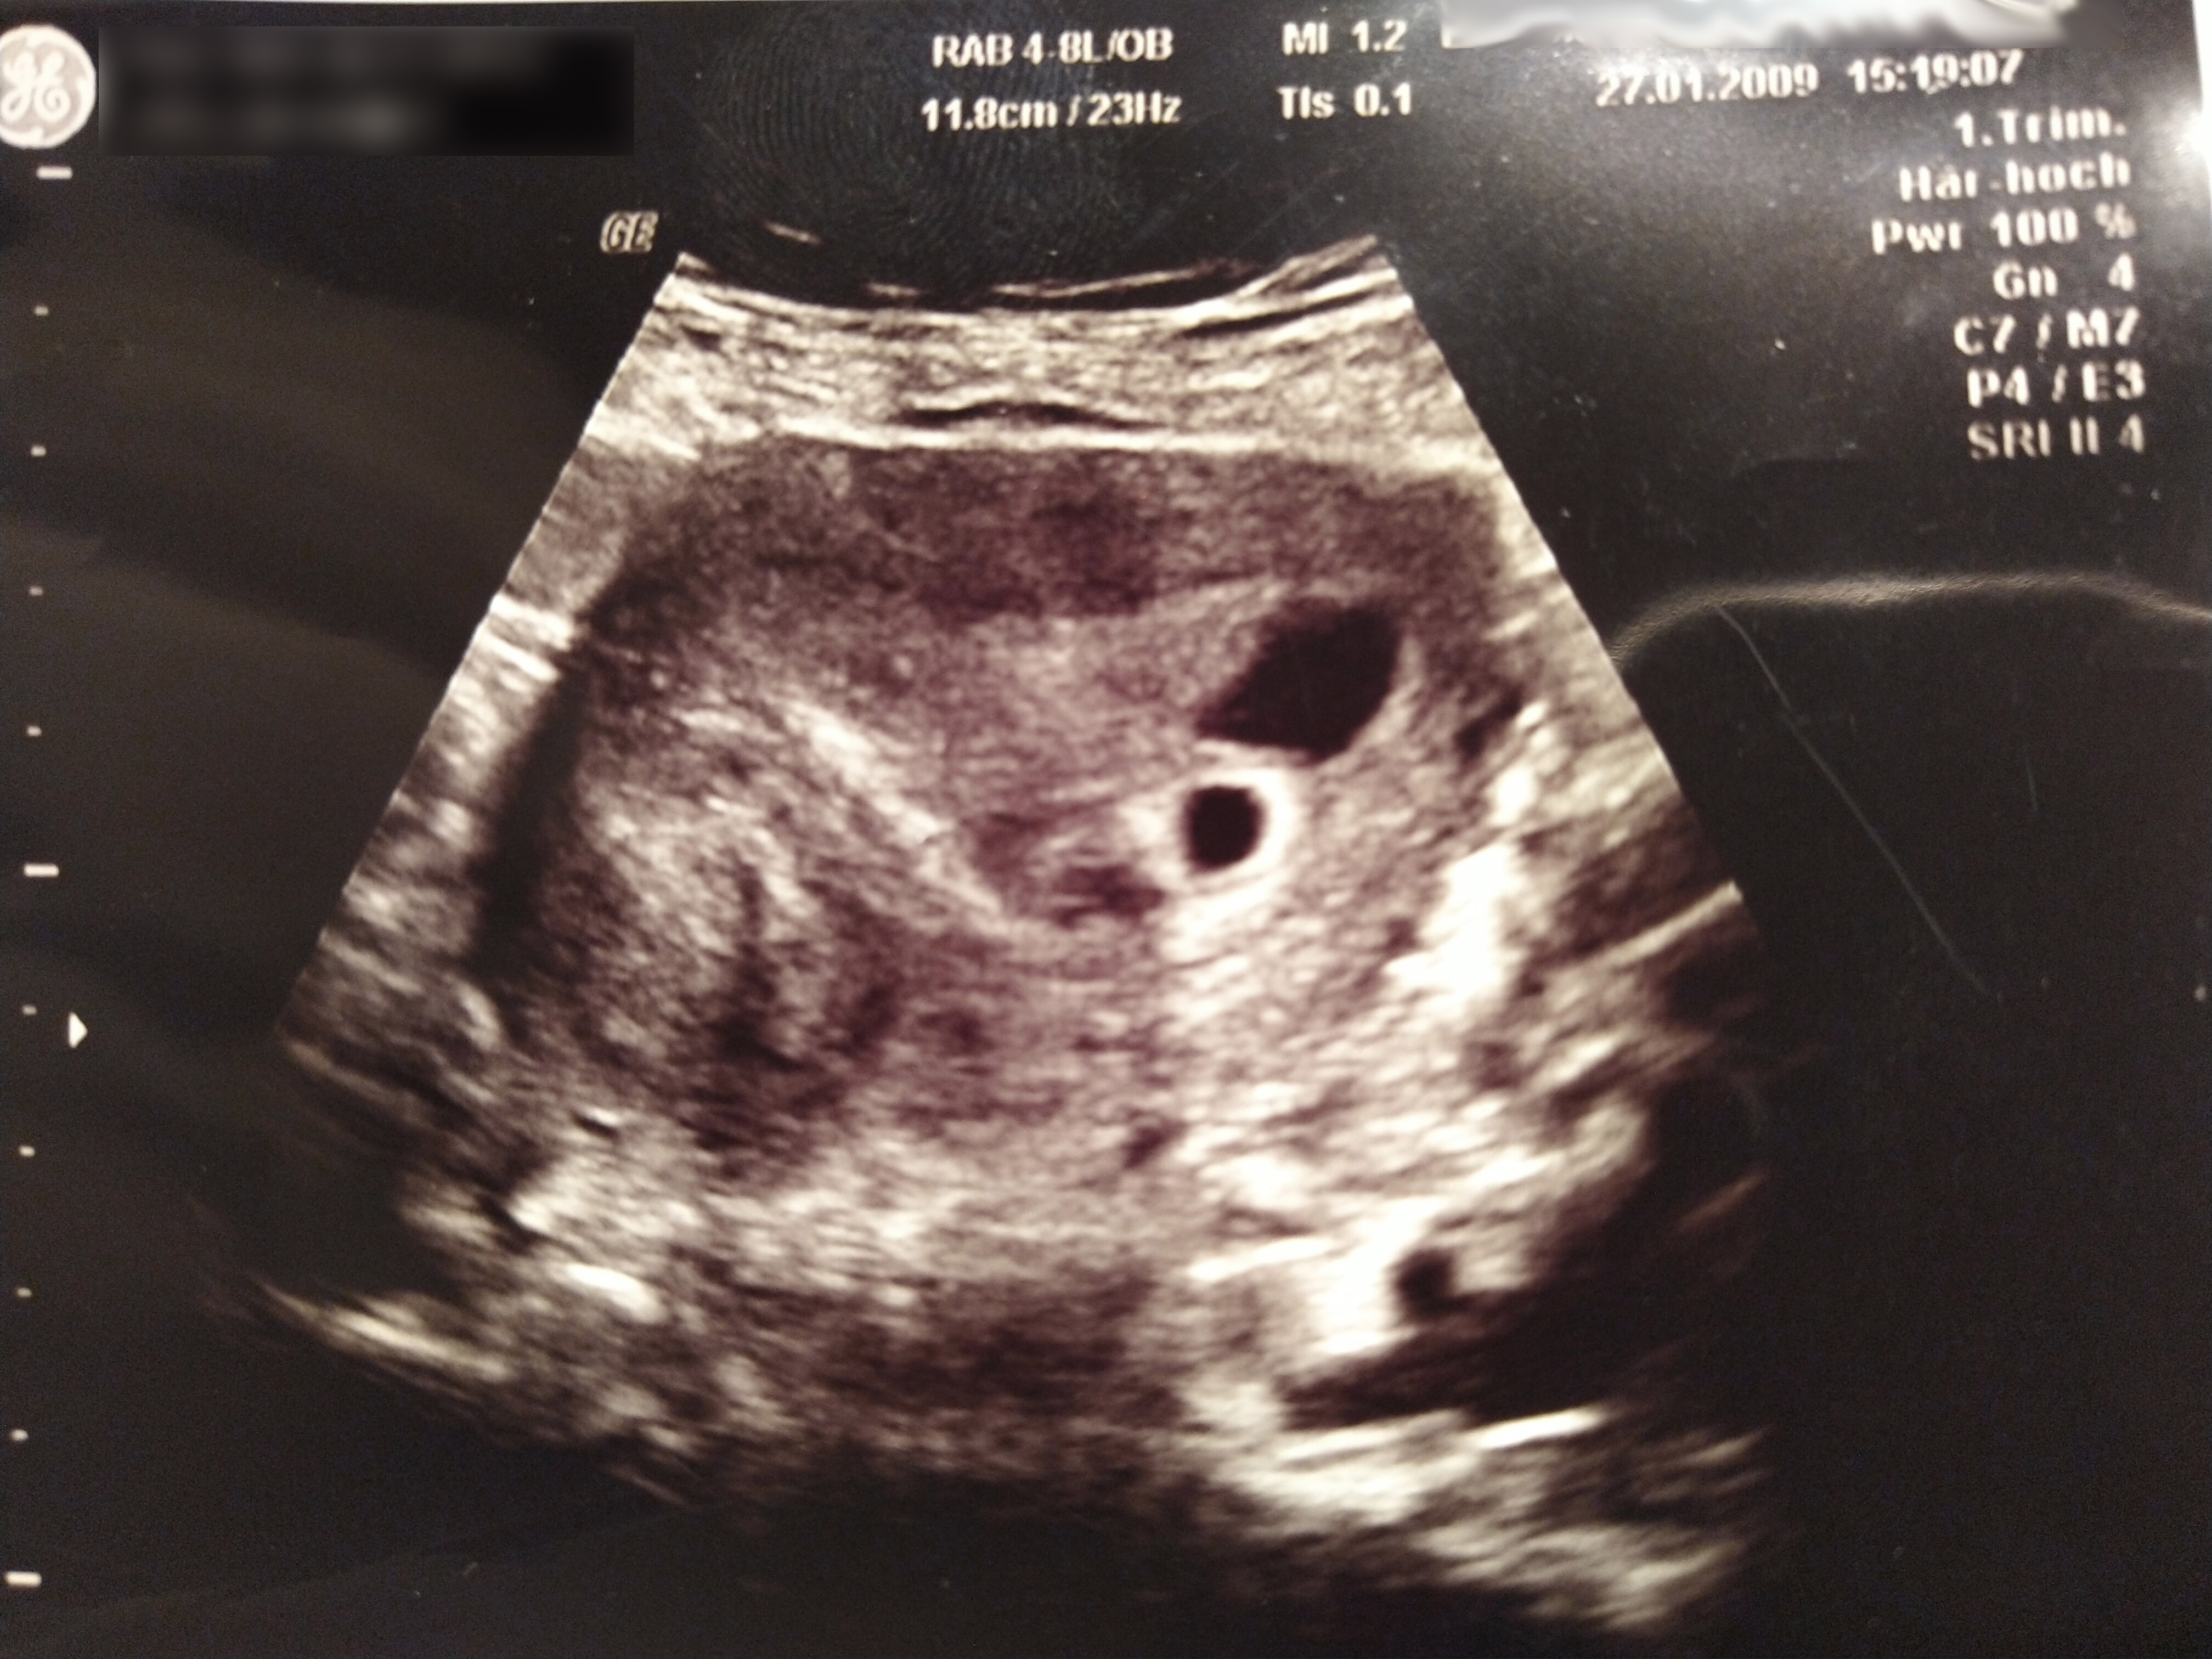

Ich weiß nicht wie viele Tage ins Land gingen, wie groß Karl-Uwe schon geworden war, bis ich endlich auf dem Gyn-Stuhl meiner Frauenärztin die Beine breit machen durfte. Sie bestätigte mir die intakte Schwangerschaft, fragte mich NOCH mal, ob ich mir wirklich sicher sei fuck you! und dann spielte sie mir die Herztöne von Karl-Uwe vor…